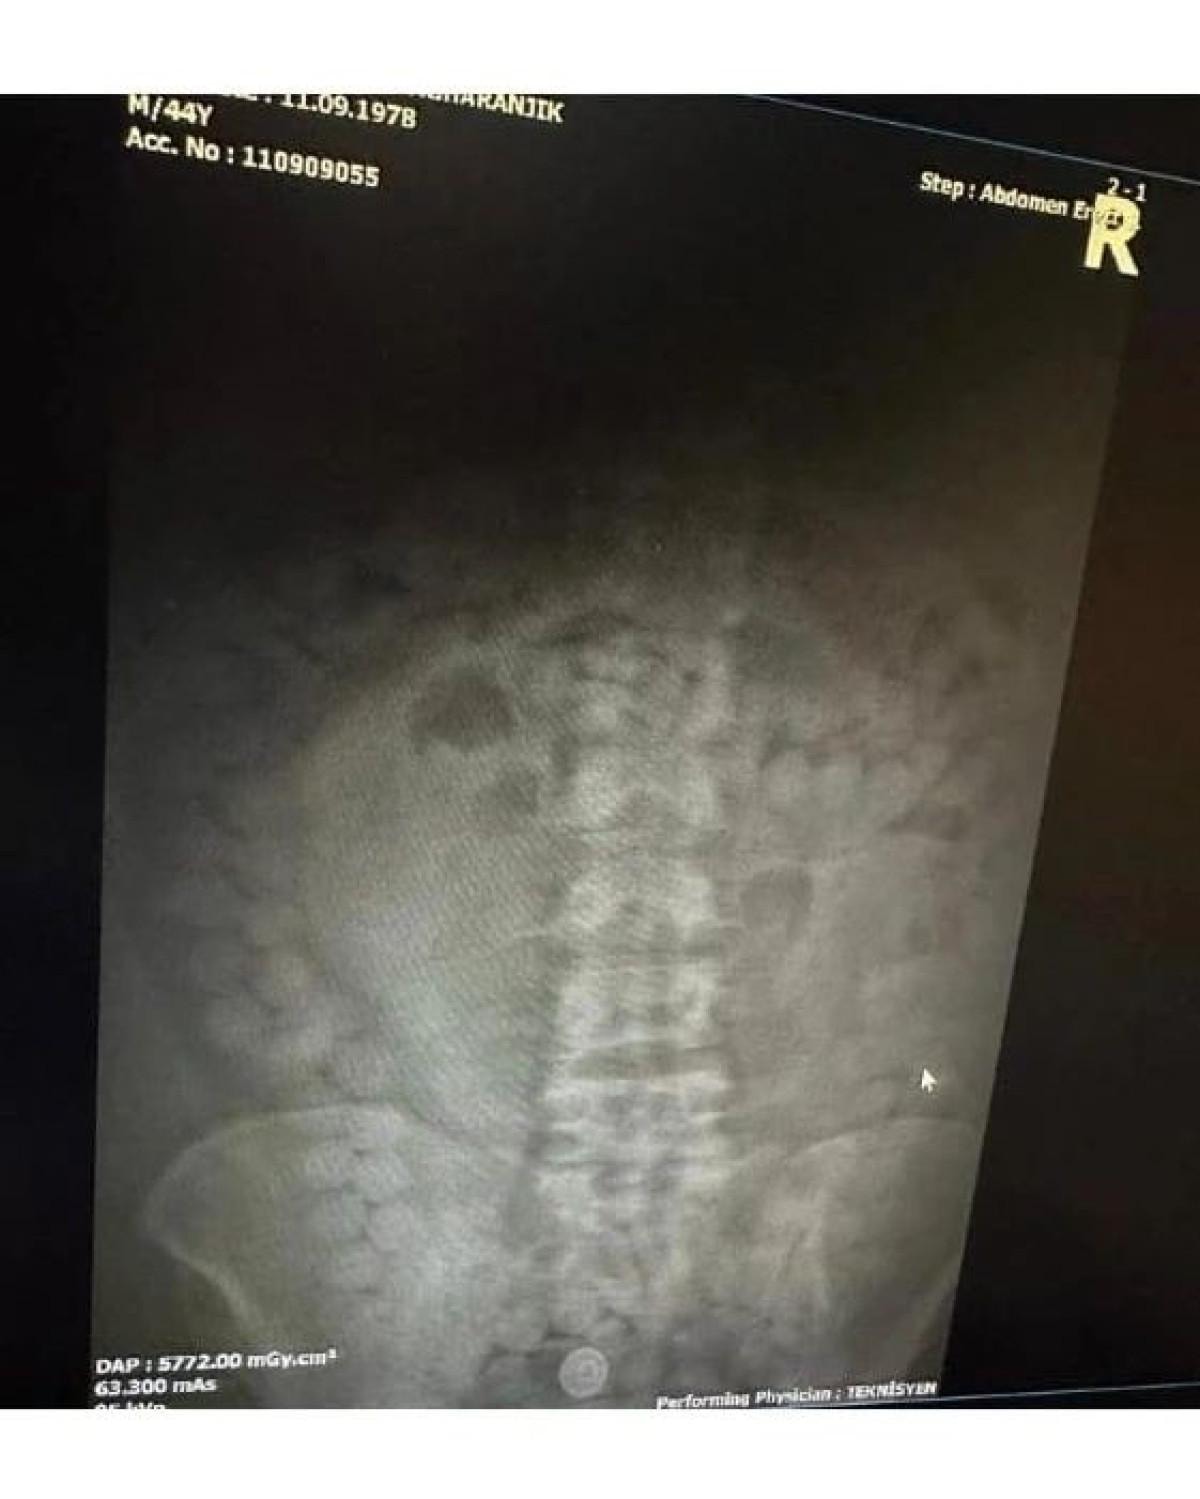

Mide ve bağırsağında uyuşturucu cisim bulundu

Bu kapsamda İran uyruklu M.Z. (45) isimli şahıstan şüphelenilmesi sonucu iç beden muayenesi kararına istinaden yapılan tomografi çekiminde mide ve bağırsak kısmında uyuşturucu olabileceği değerlendirilen çokça yabancı cismin olduğu görüldü.

Yapılan tetkikler neticesinde M.Z. isimli şahıstan 101 adet kapsül halinde 848,82 gram Afyon sakızı ele geçirildi.